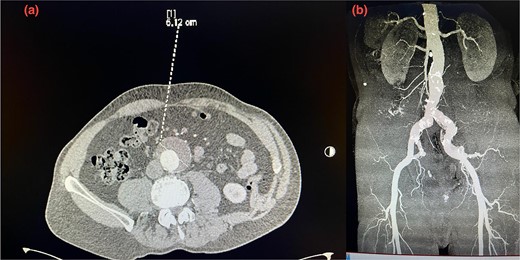

A 75-year-old patient presented with recurrent episodes of acute limb ischemia described as burning pain and pallor in the right leg. The patient’s medical history included hypercholesterolemia, hypertension, a 20-pack-year smoking history, and no significant surgical history prior to the AAA diagnosis. He was prescribed aspirin 325 mg and atorvastatin 40 mg for hypercholesterolemia and cardiovascular disease prevention; however, the patient was non-adherent to these medications. Lipid profile at the time of presentation showed increased cholesterol levels, with a low-density lipoprotein (LDL) of 190 mg/dL, HDL of 42 mg/dL, and triglycerides of 250 mg/dL. He was transferred to our hospital with a diagnosis of an AAA measuring 6.12 cm. The aneurysm had a healthy 2 cm infrarenal neck and bilateral common iliac artery ectasia, with the right common iliac artery measuring 2.9 cm and the left measuring 2.4 cm (Fig. 1a and b). Computed tomography (CT) imaging also revealed a 5 cm atheromatous plaque at the hypogastric arteries.

(a) Pre-operative axial CT scan of the infrarenal aorta showing an aneurysm (arrow) measuring 6.10 cm. (b) Initial CTA scan. A detailed anatomy of the bilateral iliac arteries is presented, and the axial image of the CTA demonstrated bilateral common iliac artery ectasia, measuring 2.9 cm on the right side and 2.4 cm on the left side.